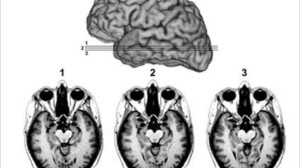

L’epilessia è la malattia neurologica più comune tra i bambini, ne soffre infatti lo 0,5 per cento di tutti i bambini di età compresa tra i 2 e i 10 anni. Durante l’infanzia, lo sviluppo nervoso del cervello è nella sua fase più intensa e l’epilessia è caratterizzata dalla remissione, questo significa che le crisi si presentano e durano per un po’ prima di scomparire completamente. Una crisi epilettica è causata da un disturbo elettronico delle funzioni cerebrali. L’epilessia forma un gruppo eterogeneo di sindromi del sistema nervoso all’interno delle quali le cause, l’età dell’insorgenza e le cure variano significativamente. L’epilessia è più comune tra coloro che si trovano sui lati opposti dello spettro di età: i bambini piccoli e gli anziani.

I meccanismi esatti che causano la remissione rimangono sconosciuti e questa scoperta del nuovo gene del cane da parte degli scienziati potrebbe aiutare i ricercatori a capire meglio come si sviluppa il cervello dei bambini e a far luce sui meccanismi di remissione nell’epilessia infantile.

“Con questo studio, otteniamo informazioni importantissime sulle vie nervose e sui meccanismi che controllano lo sviluppo del cervello di un bambino, ottimizzando la sua struttura per la stabilità elettrica e per eliminare le crisi per il resto della vita adulta. Questo studio preparerà il terreno per la ricerca volta a scoprire le basi molecolari della trasformazione del cervello dallo stato immaturo dell’infanzia alle sue massime capacità nell’adolescenza e nella prima fase dell’età adulta,” dice il dott. Berge Minassian, un altro autore dello studio che lavora presso The Hospital for Sick Children di Toronto, Canada.